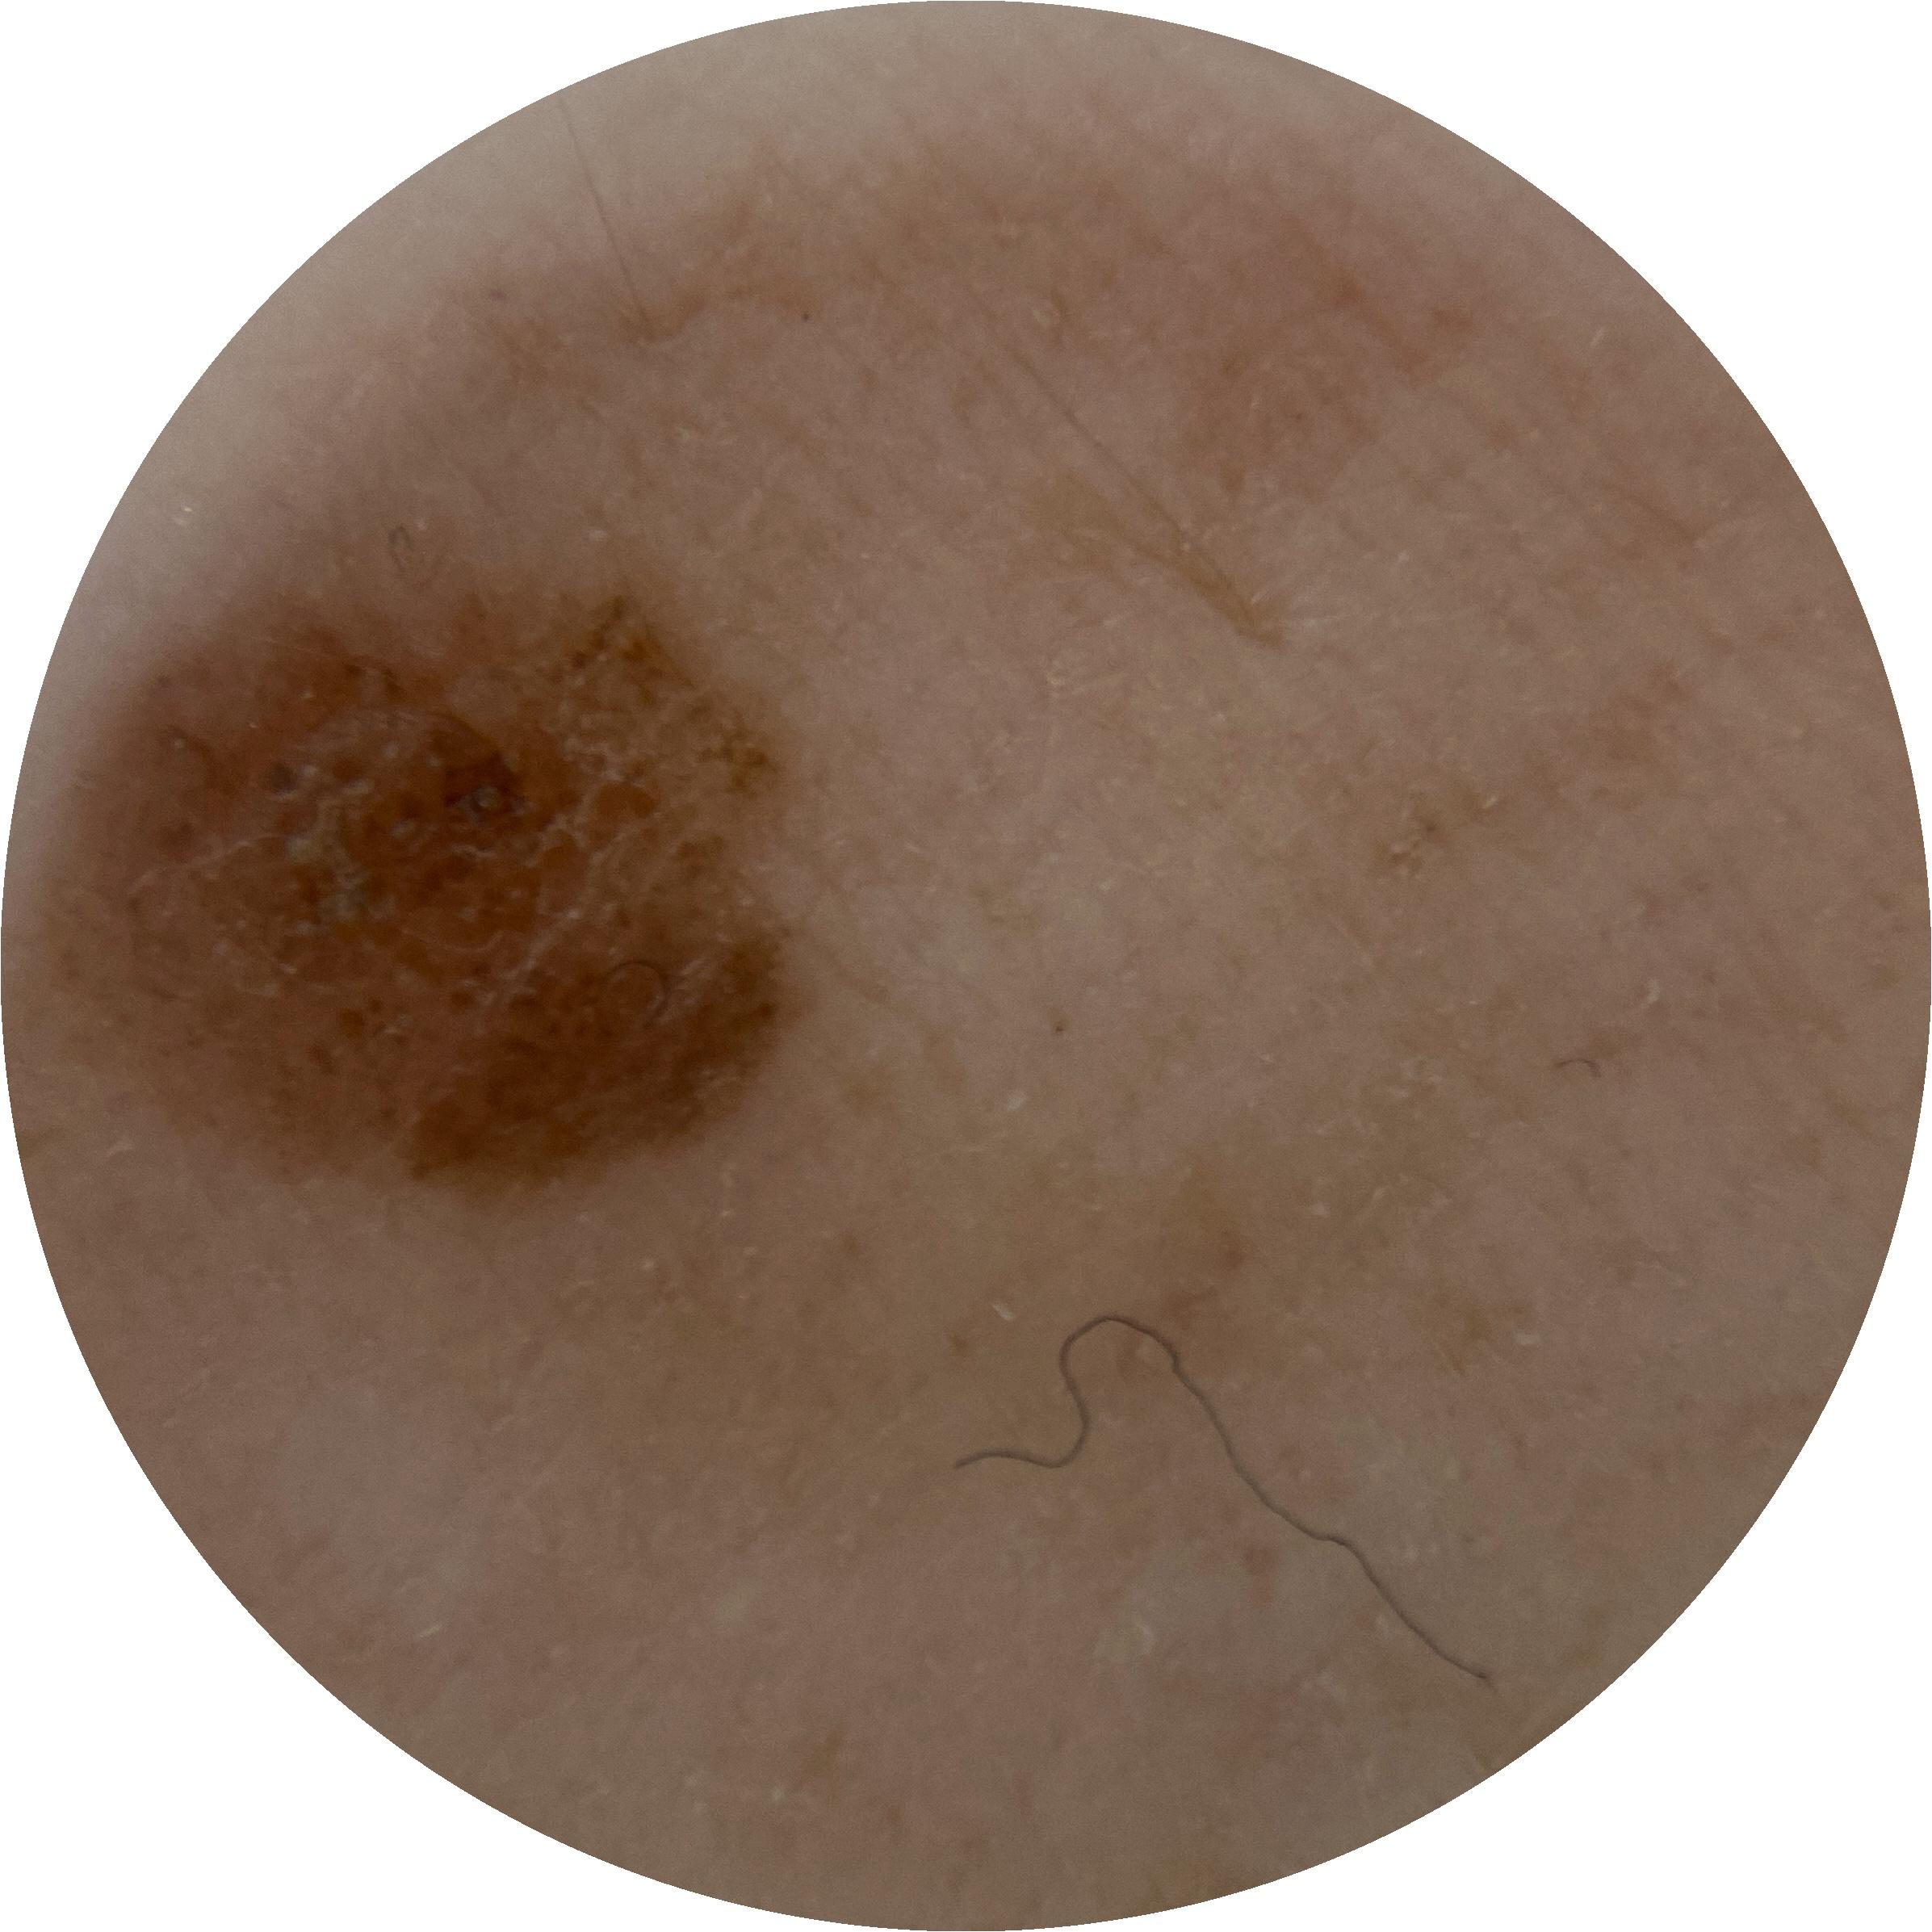

ISIC_3411919

Information

2643 x 2643

MEL-SELF Trial, https://www.sydney.edu.au/medicine-health/our-research/research-centres/melself-project.html

Clinical

Field Value

acquisition_day 308

age_approx 60

anatom_site_1 Upper extremity

anatom_site_general upper extremity

diagnosis_1 Benign

diagnosis_confirm_type single image expert consensus

fitzpatrick_skin_type I

image_type dermoscopic